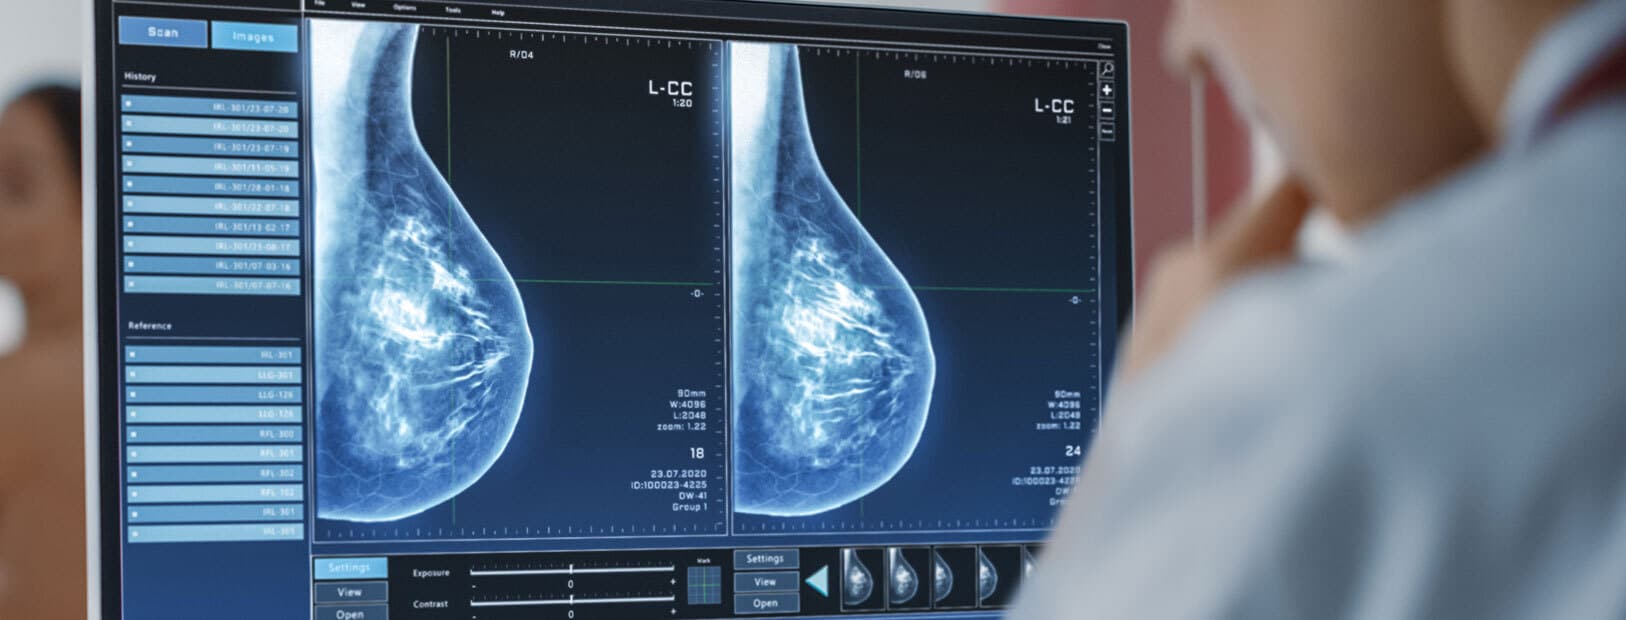

80 % des cancers du sein sont diagnostiqués après 50 ans, dont 50 % entre 50 et 69 ans. C’est pourquoi toutes les femmes âgées de 50 à 74 ans sont invitées à participer au dépistage du cancer du sein. Il repose sur une mammographie tous les deux ans, prise en charge à 100 % par l’Assurance Maladie. Une deuxième lecture systématique des mammographies jugées normales est assurée, par sécurité, par un second radiologue.

La mammographie utilise les rayons X pour détecter des anomalies, notamment les microcalcifications. L’échographie mammaire, elle, repose sur les ultrasons et complète souvent la mammographie, particulièrement chez les femmes aux seins denses. Bien que seule la mammographie soit recommandée de façon systématique, les deux examens sont fréquemment associés pour un dépistage optimal.

Détecter un cancer du sein grace à l'odorat du chien ne peut être utilisé pour le dépistage du cancer du sein; mais il fait l'objet de projets de recherche. En 2017, 2 chiens éduqués ont réussi à détecter 90,3% des échantillons positifs parmi les 130 échantillons de sueur qui leur étaient présentés. Pour aller plus loin et tester cette hypothèse une première étude clinique a été menée entre 2020 et 2022; les résultats n’ont certes pas été suffisants, mais restent plus qu’encourageants pour l’avenir de la détection canine du cancer du sein. La mammographie reste donc aujourd'hui l'unique instrument reconnu et utilisé pour diagnostiquer le cancer du sein.